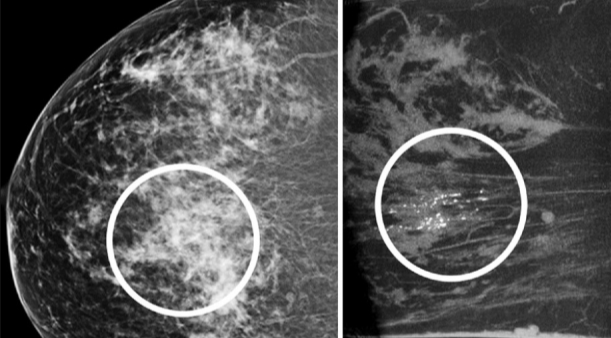

Mammogram Microcalcification Detection

ML Python Scikit-learn

Github Repo